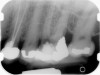

Fig 9 Preoperative radiographs showing mesial perforation.

Figure 9

Fig 10. Preoperative radiographs showing mesial perforation.

Figure 10